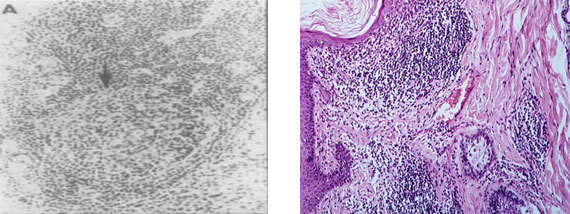

На рис. 5 представлены лимфоплазмоцитарные инфильтраты при ревматоидном синовите, принимающие формы фолликулоподобных структур и иммуногистохимическую идентификацию хемокина CXCL13 в этих структурах в синовиальной оболочке при РА в крайнем справа фото.

Рис. 5. Слева (А, В) видны лимфоплазмоцитарные инфильтраты при ревматоидном синовите, принимающие формы фолликулоподобныхструктур (Х 100), по материалам [160] Крайний справа снимок отражает иммуногистохимическую идентификацию хемокина CXCL13 (указано стрелками) в фолликулоподобной структуре в синовиальной оболочке при РА (Х 100), по материалам [68]

Фолликулоподобные структуры включают в себя макрофаги (CD68+), Т-лимфоциты (CD4+), В-лимфоциты (CD20+), дендритные клетки (CD303+). При РА в них определяются большие клеточные агрегаты, включающие скопления фДК, обладающих высокой АГ-презентирующей способностью [122].